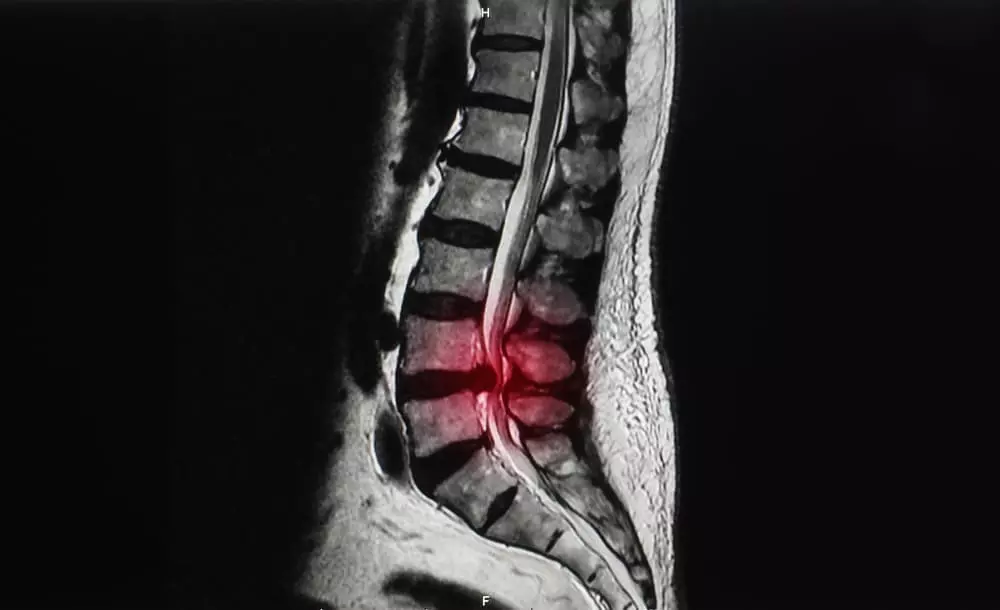

After

脊柱管狭窄症とは?

体を支える脊柱は、椎骨という骨が連結してできています。

その椎骨には穴が存在し、脊柱として形成されたときには脊柱管という脊髄・血管が走る道が作られます。

その脊柱管が加齢や何かの要因でズレが生じ狭まったときに発症するのが脊柱管狭窄症です。

脊柱管が狭くなると、内部を走っている脊髄や血管が押し付けられます。

それにより

痛みやしびれといった症状が現れます。